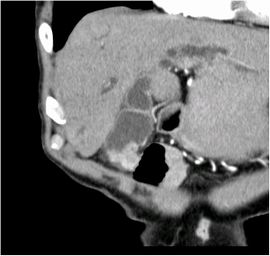

CT検査にて胆嚢底部に限局性に壁肥厚を認め、精査の結果、悪性病変疑いと診断。腹腔鏡下胆嚢摘出術を施行した。病理結果は胆嚢がんであった。

CT画像